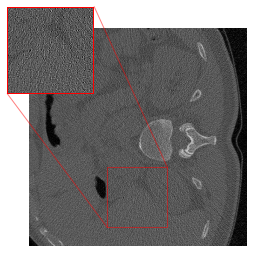

The methodology from DRUNet and its predecessor FFDNet [69] involves segmenting the input image into four distinct corner parts, each processed separately through the network. Zhang et al. [17] utilize images with identically distributed Gaussian noise, allowing for individual denoising of sub-images and recombination without noticeable artifacts at the patch boundaries. However, our application of this strategy in CT results in artifacts at the patch boundaries (cf. Figure 2(c)), showcasing a sudden shift from intense to subtle smoothing with the cropping strategy. This issue may arise because the errors in CT images are not simply Gaussian noise, but rather a more complex mixture of noise types, including Poisson noise that has been log-transformed and then backpropagated via FBP. For mitigating the artifacts, we modify the cropping approach of [69] by implementing padding in the output of the FBP to align with the network architecture. The DRUNet architecture operates solely on images sized as multiples of 24=16superscript24162^{4}=162 start_POSTSUPERSCRIPT 4 end_POSTSUPERSCRIPT = 16 due to its four downsampling steps, whereas the LoDoPaB-CT dataset comprises images of size 362×362362362362\times 362362 × 362, which does not conform to this requirement. To address this, we apply mirror padding to enlarge the images to 368×368368368368\times 368368 × 368 before passing them through the network and subsequently cropping them back to the original size of 362×362.362362362\times 362.362 × 362 . Figure 2 illustrates the suitability of the proposed strategy. (We point out that the image depicted in Figure 2 represents one of the most challenging reconstructions within the dataset.) For the 2016LDCTGC dataset, the images are sized at 512×512512512512\times 512512 × 512, which means they do not need additional padding and can be processed directly by the network.

Figure 2: An example highlighting the distinction between the DRUNet and FFDNet methodology of cropping versus the adapted padding strategy. (a) shows the low-dose FBP, while (b) displays the corresponding ground truth. (c) highlights the artifacts at the patch boundaries resulting from denoising on sub-images, whereas (d) exhibits artifact mitigation achieved through ommiting the partitioning into blocks.